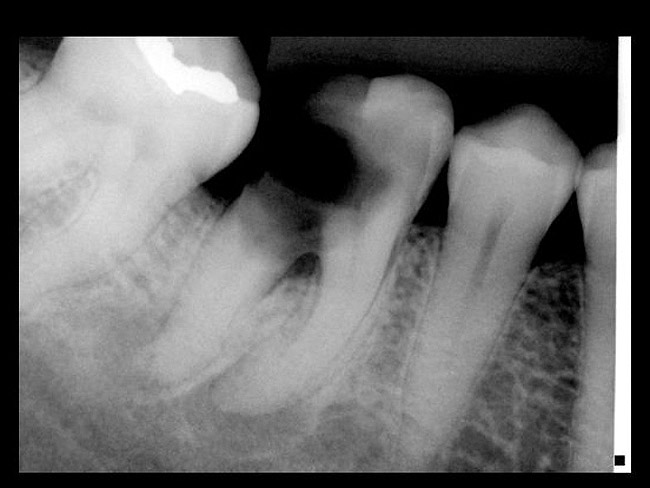

Figure 12  ENDODONTIC AND ESTHETIC PARAMETERS A tooth with a periapical radiolucency > 5 mm significantly decreases the success rate of endodontic therapy.

Figure 12